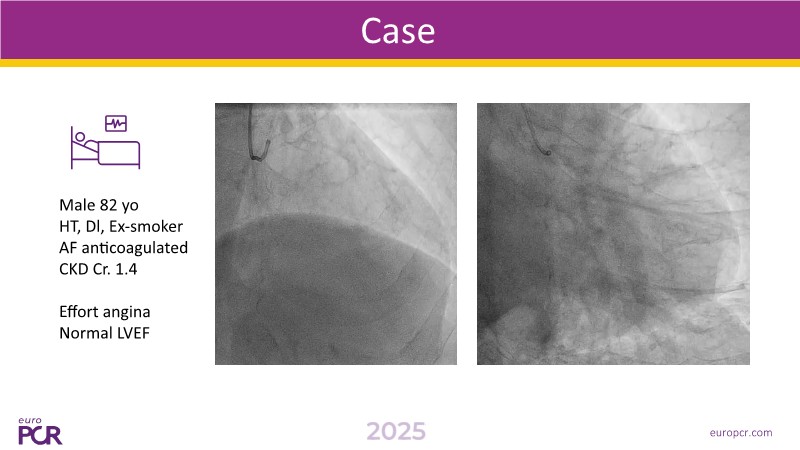

This session examines evolving catheterisation lab workflows, highlighting how integrated imaging, physiology, and procedural strategies are reshaping PCI practices. Speakers emphasize the importance of advanced pre-procedural planning using modalities such as intravascular ultrasound (IVUS) to optimise stent deployment, and cardiac computed tomography angiography (CCTA) to improve diagnosis and minimize contrast-induced nephropathy. Illustrated by real-life clinical cases, the session demonstrates how combining imaging and physiology with angiography improves workflow efficiency, enhances procedural quality, and reduces both radiation exposure and contrast volume. The session concludes with a call to adopt this integrated, technology-enabled PCI approach to better address the growing complexity of interventional cardiology cases.